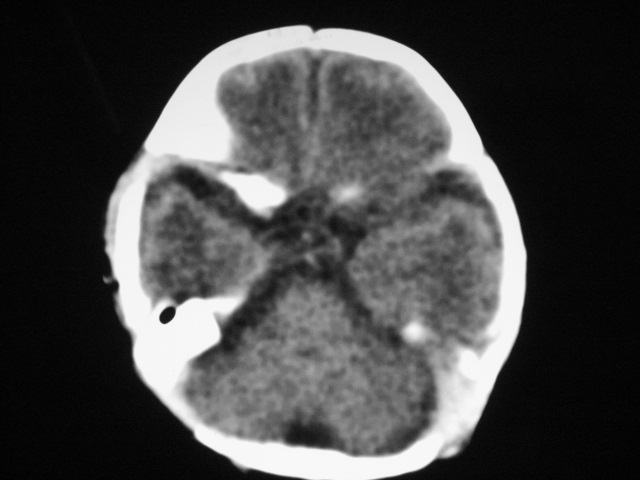

早产儿,1天,饮食呕吐,

支持;新生儿缺血缺氧性脑病伴少量蛛网膜下腔出血.

支持;新生儿缺血缺氧性脑病伴少量蛛网膜下腔出血

支持;新生儿轻度缺氧缺血性脑病伴少量蛛网膜下腔出血.

患儿头颅ct示:皮质薄,髓质密度减低,脑回宽,脑沟浅,脑室系统无殊,中线结构居中,符合:早产儿颅脑ct改变。

1hie2珠网膜下腔出血(少量)